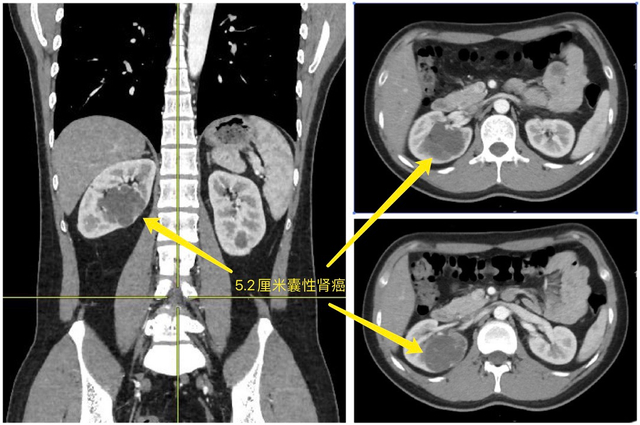

患者张博士目前在国内顶尖学府从事科学研究工作,经体检发现双肾多发性囊肿。其中较大的一个囊肿位于右肾,直径达5.2厘米,内部有多发分隔,囊性肾病Bosniak分级为IV级,提示为囊性肾细胞癌。

九院泌尿外科主任徐斌接诊后根据已有资料分析评估,表示保肾手术可以实现。患者右肾囊性肿瘤已占据近半个肾脏,位置深,并突入肾脏核心区肾窦,肿瘤周围还密布血管和集合系统,犹如一枚藏在体内的薄皮炸弹,手术过程中集合系统一旦破损,将有尿外渗的风险;如血管有破裂,则有大出血的风险。

再者,该囊性肿瘤囊壁薄如蝉翼,不同于普通囊肿,囊液内可能漂浮着癌细胞,必须完整切除囊肿、且不破损囊壁,否则癌细胞将随着囊液广泛播散,手术切除范围广,切除后创面大,缝合难度高。